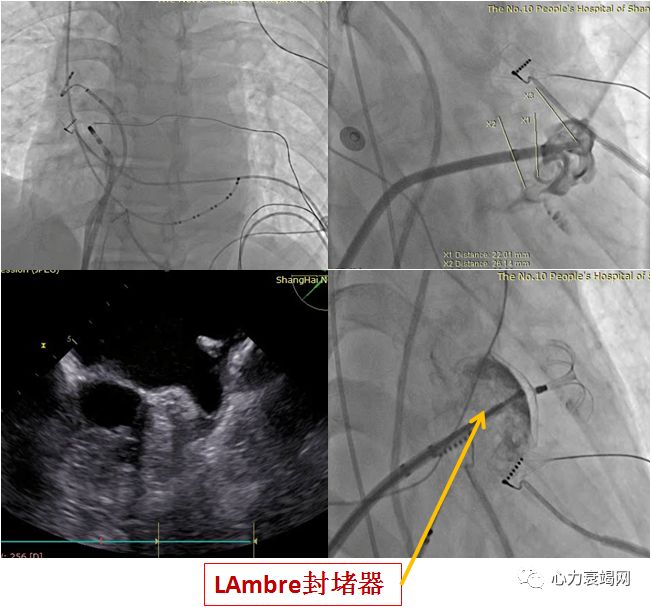

Lifetech LAmbreTMDevice(中国人的发明)

小推送鞘(8~10F) 释放简单, 可回收,可再次定位, 可以行MRI

左心耳封堵器- LAmbreTM Device

夏XX,61岁,女性,因“反复心悸1年余,再发8月”入院

1年前,在我院初诊”房颤”,植入单腔起搏器,术后予华法林抗凝,服用不规律,INR未按医嘱监测

HTN10余年,1年前“脑梗”1次, “心尖肥厚型心肌病”病史

心电图: 房颤律,心室起搏

实验室检查:cTnT, ng/ml 0.085 (<0.014 正常), INR 1.27

TTE:LA内径 48mm,LVEF 58%,二尖瓣轻度反流

TEE:LA后前径55mm, LAA单叶, 开口内径22mm, 深度37mm

诊断: 房颤, 永久型, 单腔起搏器术后

CHADS2:3分, CHA2-DS2-VASC :4分

造影提示:LAA开口最大23.4mm

术前及术中TEE测量45º、60º、90º、135º提示开口最大22mm,深度38mm

选择28mm*34mm的LAmbre封堵器